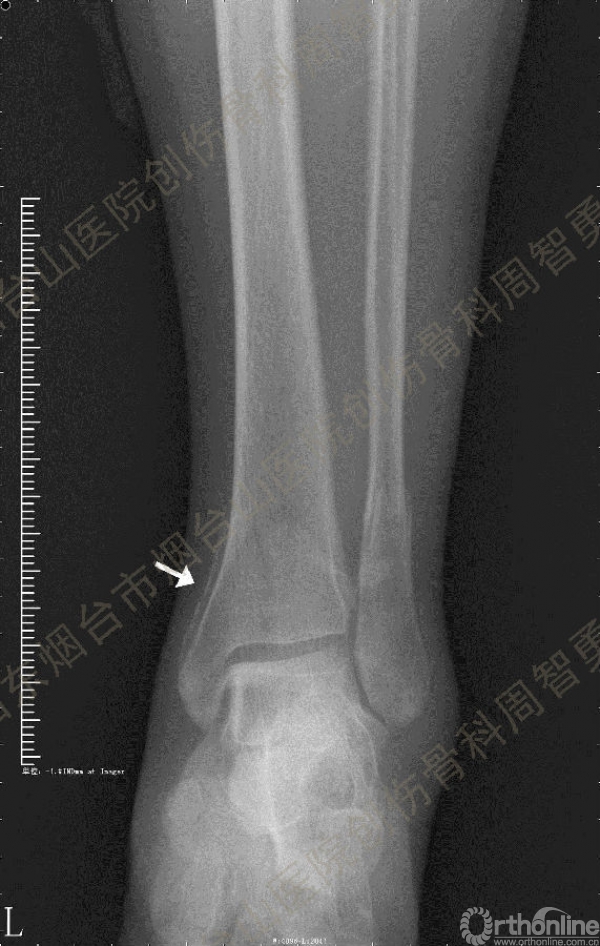

患者一般情况可,左踝关节肿胀,见皮下瘀斑,内、外、后侧有压痛,左踝关节主动运动受限,左足皮肤感觉、血供未见明显异常,左足趾各关节可主动运动。左踝关节正位X线片和CT重建示内踝内上方双层骨皮质影(图1a,c),CT示后侧骨折块分为后内侧骨折块和后外侧骨折块(图2a,b),后内侧骨折块累及内踝后丘,后丘骨折线呈冠状位(图2c),后内侧骨折块腹侧有向近端塌陷的小块骨软骨骨折块(图2d),CT也显示Chaput骨折块(图1c,2e)。

经典的后踝骨折发生于低能量旋转外力所致的踝关节骨折;标准pilon骨折见于高能量轴向暴力;而后侧pilon骨折是旋转外力和轴向暴力共同作用的结果,属于中等能量的损伤。踝关节骨折中的后踝骨折源自下胫腓后韧带的牵拉,骨折块位于后外侧,常为单一的三角形骨折块,大小从关节外片状骨折到累及胫骨远端关节面矢状径的40%(图4a)。后侧pilon骨折中的后侧骨折块较大,累及内踝后丘(三角韧带深层起点)在内的整个胫骨远端后侧,分为后内侧骨折块和后外侧骨折块,后内侧骨折块腹侧有向近端塌陷的骨软骨骨折块(图4b)。后侧pilon骨折中的内踝骨折线并不是水平位而是冠状位,可合并内踝前丘骨折。后侧pilon骨折踝关节正位X线片示特异性的内踝内上方双层骨皮质影(图1a,c)。这是由于后内侧骨折块的骨折线延伸到胫骨远端骨骺和干骺端的内侧骨皮质,其移位后的边缘成像所致。水平位CT显示后侧骨折块分为后内侧骨折块和后外侧骨折块,矢状位CT示后内侧骨折块腹侧有向近端塌陷的骨软骨骨折块。

③影像表现:踝关节正位X片显示特异性的内踝内上方双层骨皮质影

↑图 1b

图 1 术前左踝关节正侧位X线片和CT重建,箭头所示内踝内上方双层骨皮质影(a,c)